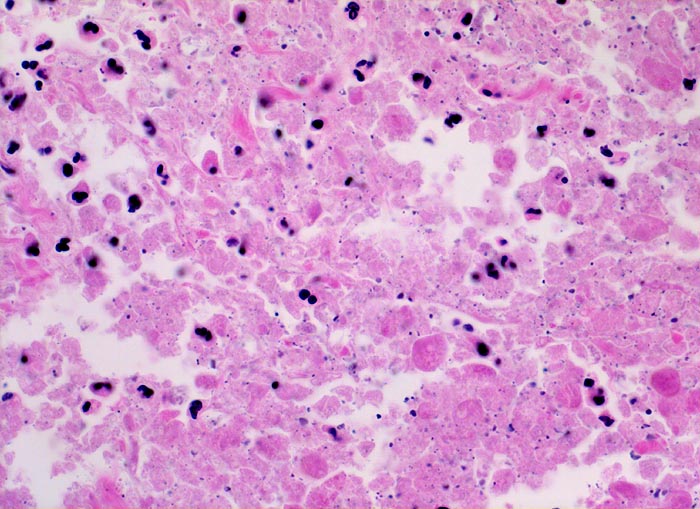

Urothelkarzinom: Tumornekrose

Nur noch schattenhaft erkennbare nekrotische Tumorzellen durchsetzt von neutrophilen Granulozyten. Die feinen schwarzen Punkte entsprechen Kerntrümmern.

Makrohämaturie. In der Harnblasenspülflüssigkeit werden Urothelien mit schweren Kernatypien vereinbar mit Urothelkarzinom nachgewiesen. Zystoskopisch kommt in der Hinterwand ein ulzerierter Tumor zur Darstellung. Die bioptische Abklärung ergibt Anteile eines wenig differenzierten Urothelkarzinoms mit ausgedehnten Nekrosen.

Gelegentlich enthalten kleine Biopsien aus einem Tumor lediglich nekrotische Tumoranteile. In solchen Fällen kann meist keine sichere Diagnose gestellt werden, da unter anderem die Kernbeurteilung als wichtiges Malignitätskriterium bei epithelialen Tumoren nicht möglich ist.